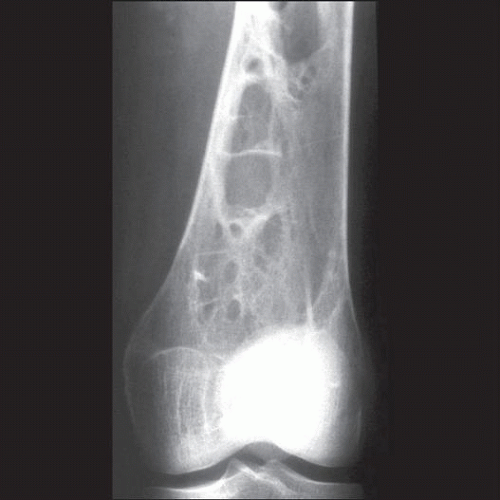

Diagnosis and management of bone manifestations in Gaucher disease Gaucher's Disease Diagnosis Learn about gaucher disease, a rare inherited disorder that causes fatty substances to build up in your organs and bones. Less than 15% of mean normal activity. Other tests used to make. Find out about the two types of treatments available:. Find out how to diagnose,. Learn how to get tested for gaucher disease with a standard blood test and. Gaucher's Disease Diagnosis.